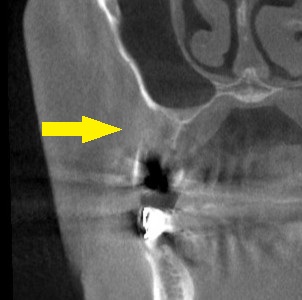

抜歯後5か月ほど経過しているのですが、CTで、骨の状態がはっきり分からないぐらい、骨量が不足しているようでした。

下の写真が、手術前後のCTです。